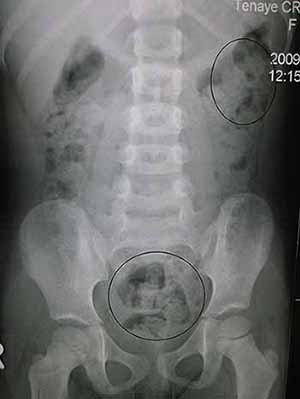

Constipation (also known as costiveness or dyschezia) refers to bowel movements that are infrequent or hard to pass. Constipation is a common cause of painful defecation. Severe constipation includes obstipation (failure to pass stools or gas) and fecal impaction, which can progress to bowel obstruction and become life-threatening.

Constipation is a symptom with many causes. These causes are of two types: obstructed defecation and colonic slow transit (or hypomobility). About 50% of patients evaluated for constipation at tertiary referral hospitals have obstructed defecation. This type of constipation has mechanical and functional causes. Causes of colonic slow transit constipation include diet, hormonal disorders such as hypothyroidism, side effects of medications, and rarely heavy metal toxicity. Because constipation is a symptom, not a disease, effective treatment of constipation may require first determining the cause. Treatments include changes in dietary habits, laxatives, enemas, biofeedback, and in particular situations surgery may be required.